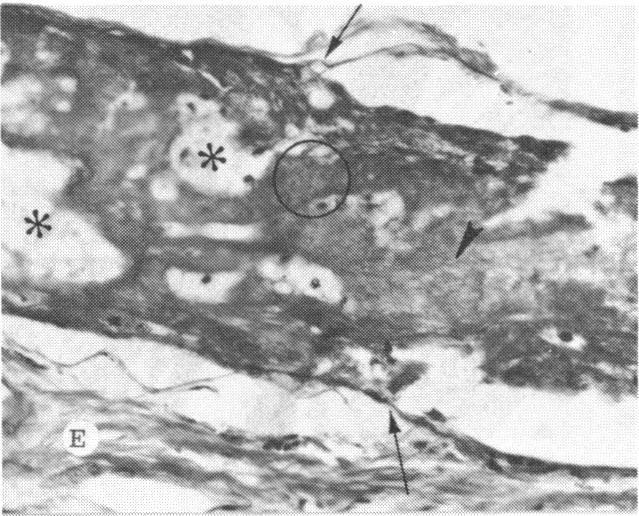

The clinical and histopathologic features of 29 eyes from 29 patients with central retinal vein occlusion (CRVO) are reported. A fresh or a recanalized thrombus was observed in each eye. This study considers the temporal aspects of the cases, and it notes the different morphologic features of the occlusion. These observations explain most of the variability of the changes observed in previous reports. We believe that these different features represent the various stages in the natural evolution of such a thrombus. The interval between CRVO and histopathologic study in our series ranged from six hours to more than 10 years. Local and systemic factors were reviewed and were found to be important in the pathogenesis of thrombus formation. Local diseases with a predisposing effect on CRVO included: glaucoma, papilledema, subdural hemorrhage, optic nerve hemorrhage, and drusen of the optic nerve head. Associated systemic diseases included: hypertension, cardiovascular and cerebrovascular disease, diabetes mellitus, and leukemia with thrombocytopenia. A fresh thrombus in the CRVO was observed in three (10.3%), and a recanalized thrombus in 26 eyes (89.7%). Endothelial-cell proliferation was a conspicuous feature in 14 (48.3%) of the eyes. Chronic inflammation in the area of the thrombus, and/or vein wall or perivenular area was observed in 14 (48.3%) of the eyes. Arterial occlusive disease was observed in seven eyes (24.6%). Cystoid macular edema was found in 26 (89.7%) of the eyes.

报告了29例视网膜中央静脉阻塞(CRVO)患者29只眼的临床和组织病理学特征。每只眼中均观察到新鲜或再通的血栓。本研究考虑了病例的时间因素,并记录了阻塞的不同形态学特征。这些观察结果解释了先前报告中观察到的变化的大部分变异性。我们认为这些不同特征代表了此类血栓自然演变的各个阶段。我们系列中CRVO与组织病理学研究之间的间隔时间从6小时到10多年不等。对局部和全身因素进行了回顾,发现它们在血栓形成的发病机制中很重要。对CRVO有 predisposing 作用的局部疾病包括:青光眼、视乳头水肿、硬膜下出血、视神经出血和视神经乳头玻璃膜疣。相关的全身疾病包括:高血压、心血管和脑血管疾病、糖尿病以及伴有血小板减少的白血病。在CRVO中观察到3只眼(10.3%)有新鲜血栓,26只眼(89.7%)有再通血栓。14只眼(48.3%)中内皮细胞增殖是一个显著特征。14只眼(48.3%)中观察到血栓区域、和/或静脉壁或静脉周围区域有慢性炎症。7只眼(24.6%)中观察到动脉闭塞性疾病。26只眼(89.7%)中发现黄斑囊样水肿。 (注:文中“predisposing”可能是“易患的”意思,但在专业医学语境中,可能有更准确特定含义,这里按常见理解翻译,具体含义需结合医学专业知识进一步确认。)